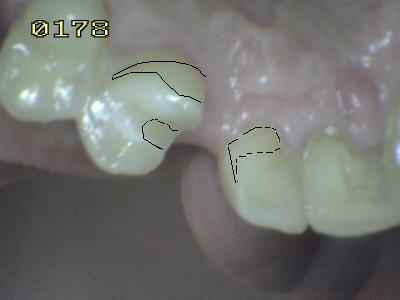

Se observa las líneas de extensión metálica del puente Maryland en las piezas talladas.